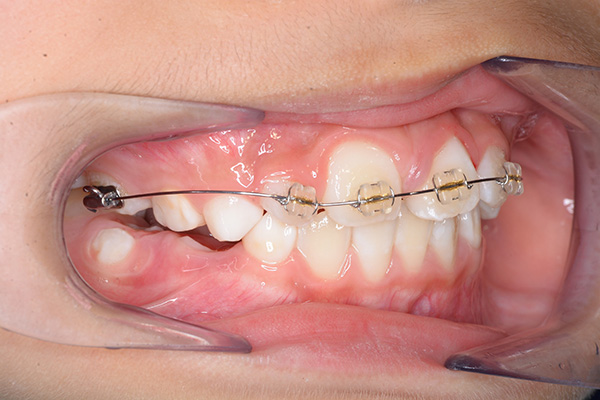

| 主訴 | 上顎前歯のでこぼこ | 診断名 | アングルⅡ級叢生症例 | ||||

|---|---|---|---|---|---|---|---|

| 初診時年齢 | 6歳9ヵ月 | 性別 | 男 | 動的治療期間 | 6ヵ月 | ||

| 使用装置 | 0.018" × 0.025" standard edgewise | ||||||

| 既往歴として上顎正中過剰歯(2本)は抜去済み。その影響で上顎右側中切歯は捻転して萌出しており、下顎右側中切歯と早期接触が認められたため2x4(上顎のみブラケット装着)にて前歯部の改善を行った。現在は永久歯列完成まで経過観察を行い、希望があれば口元の突出感を改善するために本格矯正治療を行うことにしている。 | |

| 批評・予后 | 早期治療によって前歯部の咬合干渉は回避され、その後の永久歯への交換は順調である。 |